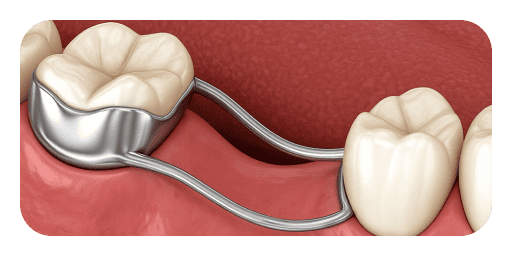

Types of Space Maintainers

Options for Treatment

Space maintainers may be fixed or removable depending on the case. Regular monitoring ensures effectiveness, comfort, and proper eruption of permanent teeth.